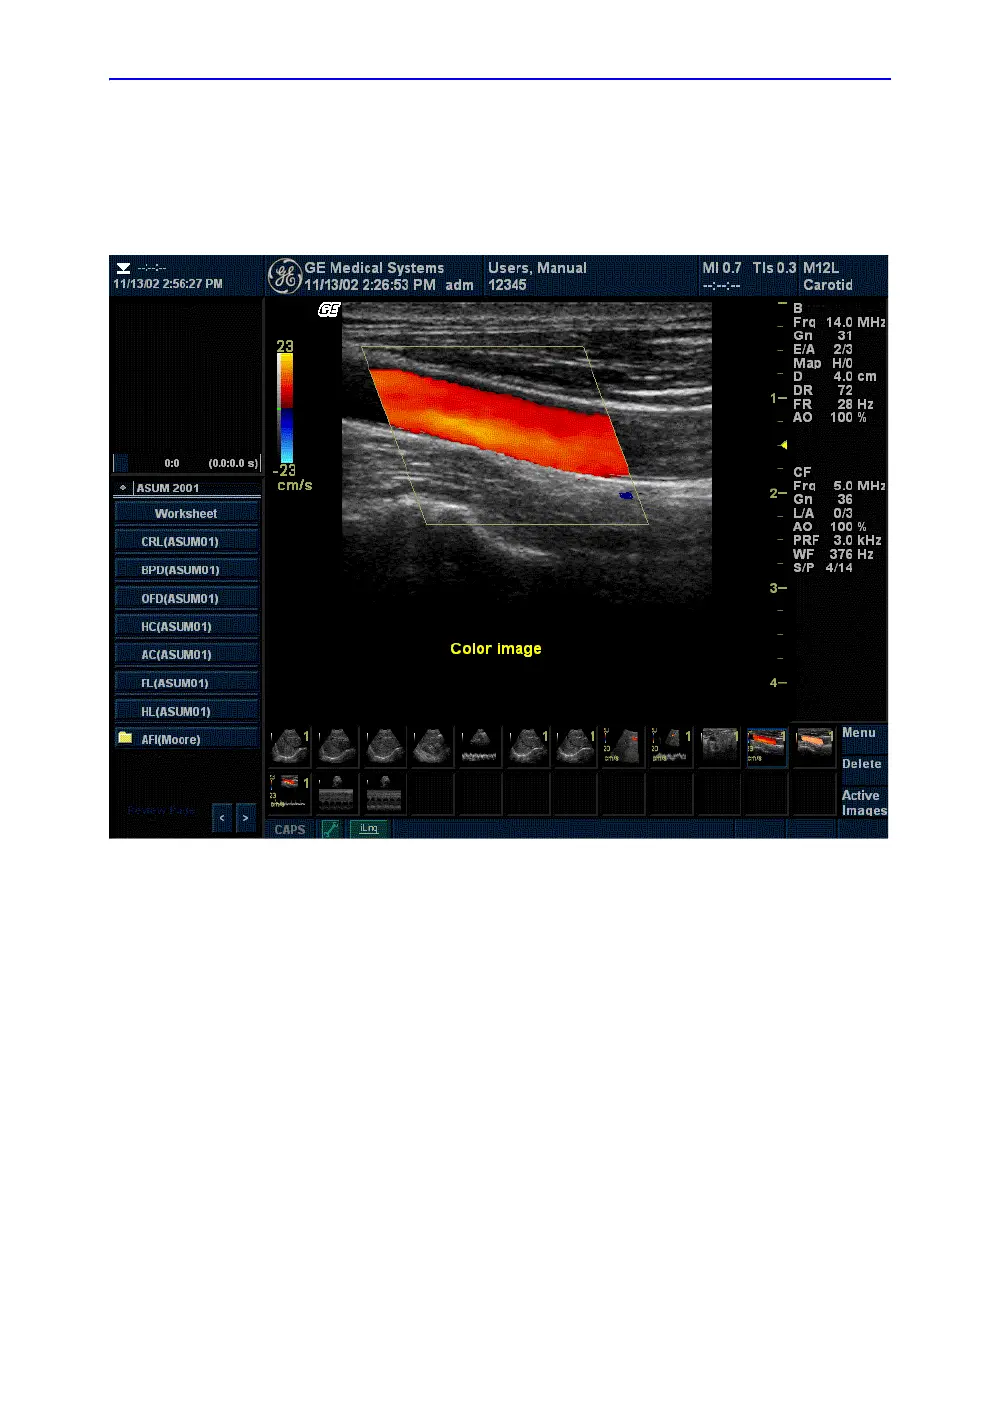

Figure 5-37. Color Flow Mode Display

Uses

Color Flow is useful to see flow in a broad area. Color Flow

allows visualization of flow in the whole image, whereas Doppler

Mode provides spectral information in a smaller area.

Color Flow is also sometimes used as a stepping stone to

Doppler. You use Color Flow to locate flow and vessels prior to

activating Doppler.